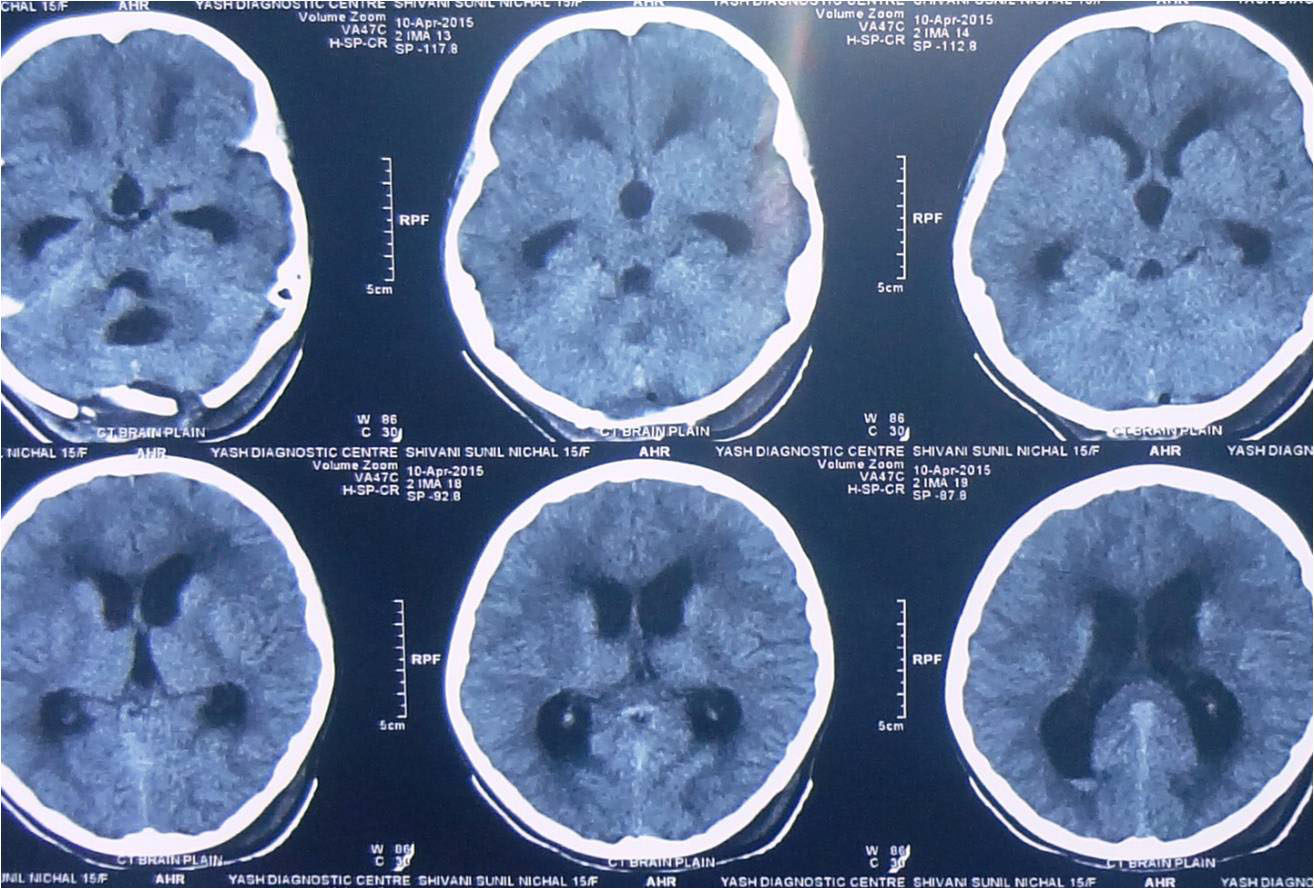

any of these symptoms he/ she should consult a neurosurgeon immediately. Usually CT Scan/ MRI of brain help

in the diagnosis. Most of the brain tumours can be safely treated by surgery but the treatment plan may vary